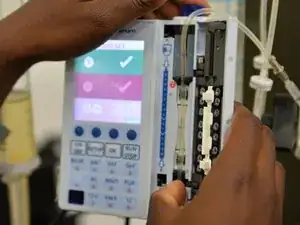

Clinical equipment refers to medical devices that are widely used in clinical settings for patient care. This includes devices like patient monitors, dialysis machines, ventilators, thermometers, stethoscopes, nebulizers, blood pressure monitors, etc.